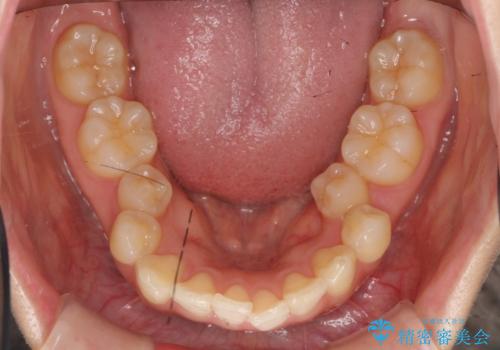

- 出っ歯を主訴に来院。

上下のかみ合わせが1本分左右ともずれていました。

②上の歯を2本抜歯、下の歯は前歯1本と最小限の抜歯(矯正治療は早く終わる、口元は下がる、抜歯は3本、上下の正中は合わない)

②を選択されました。

下顎がとても小さく後方位であるため、オトガイの閉口時のシワは完全になくすことは難しかったですが、前歯も大きく下がり満足していただきました。